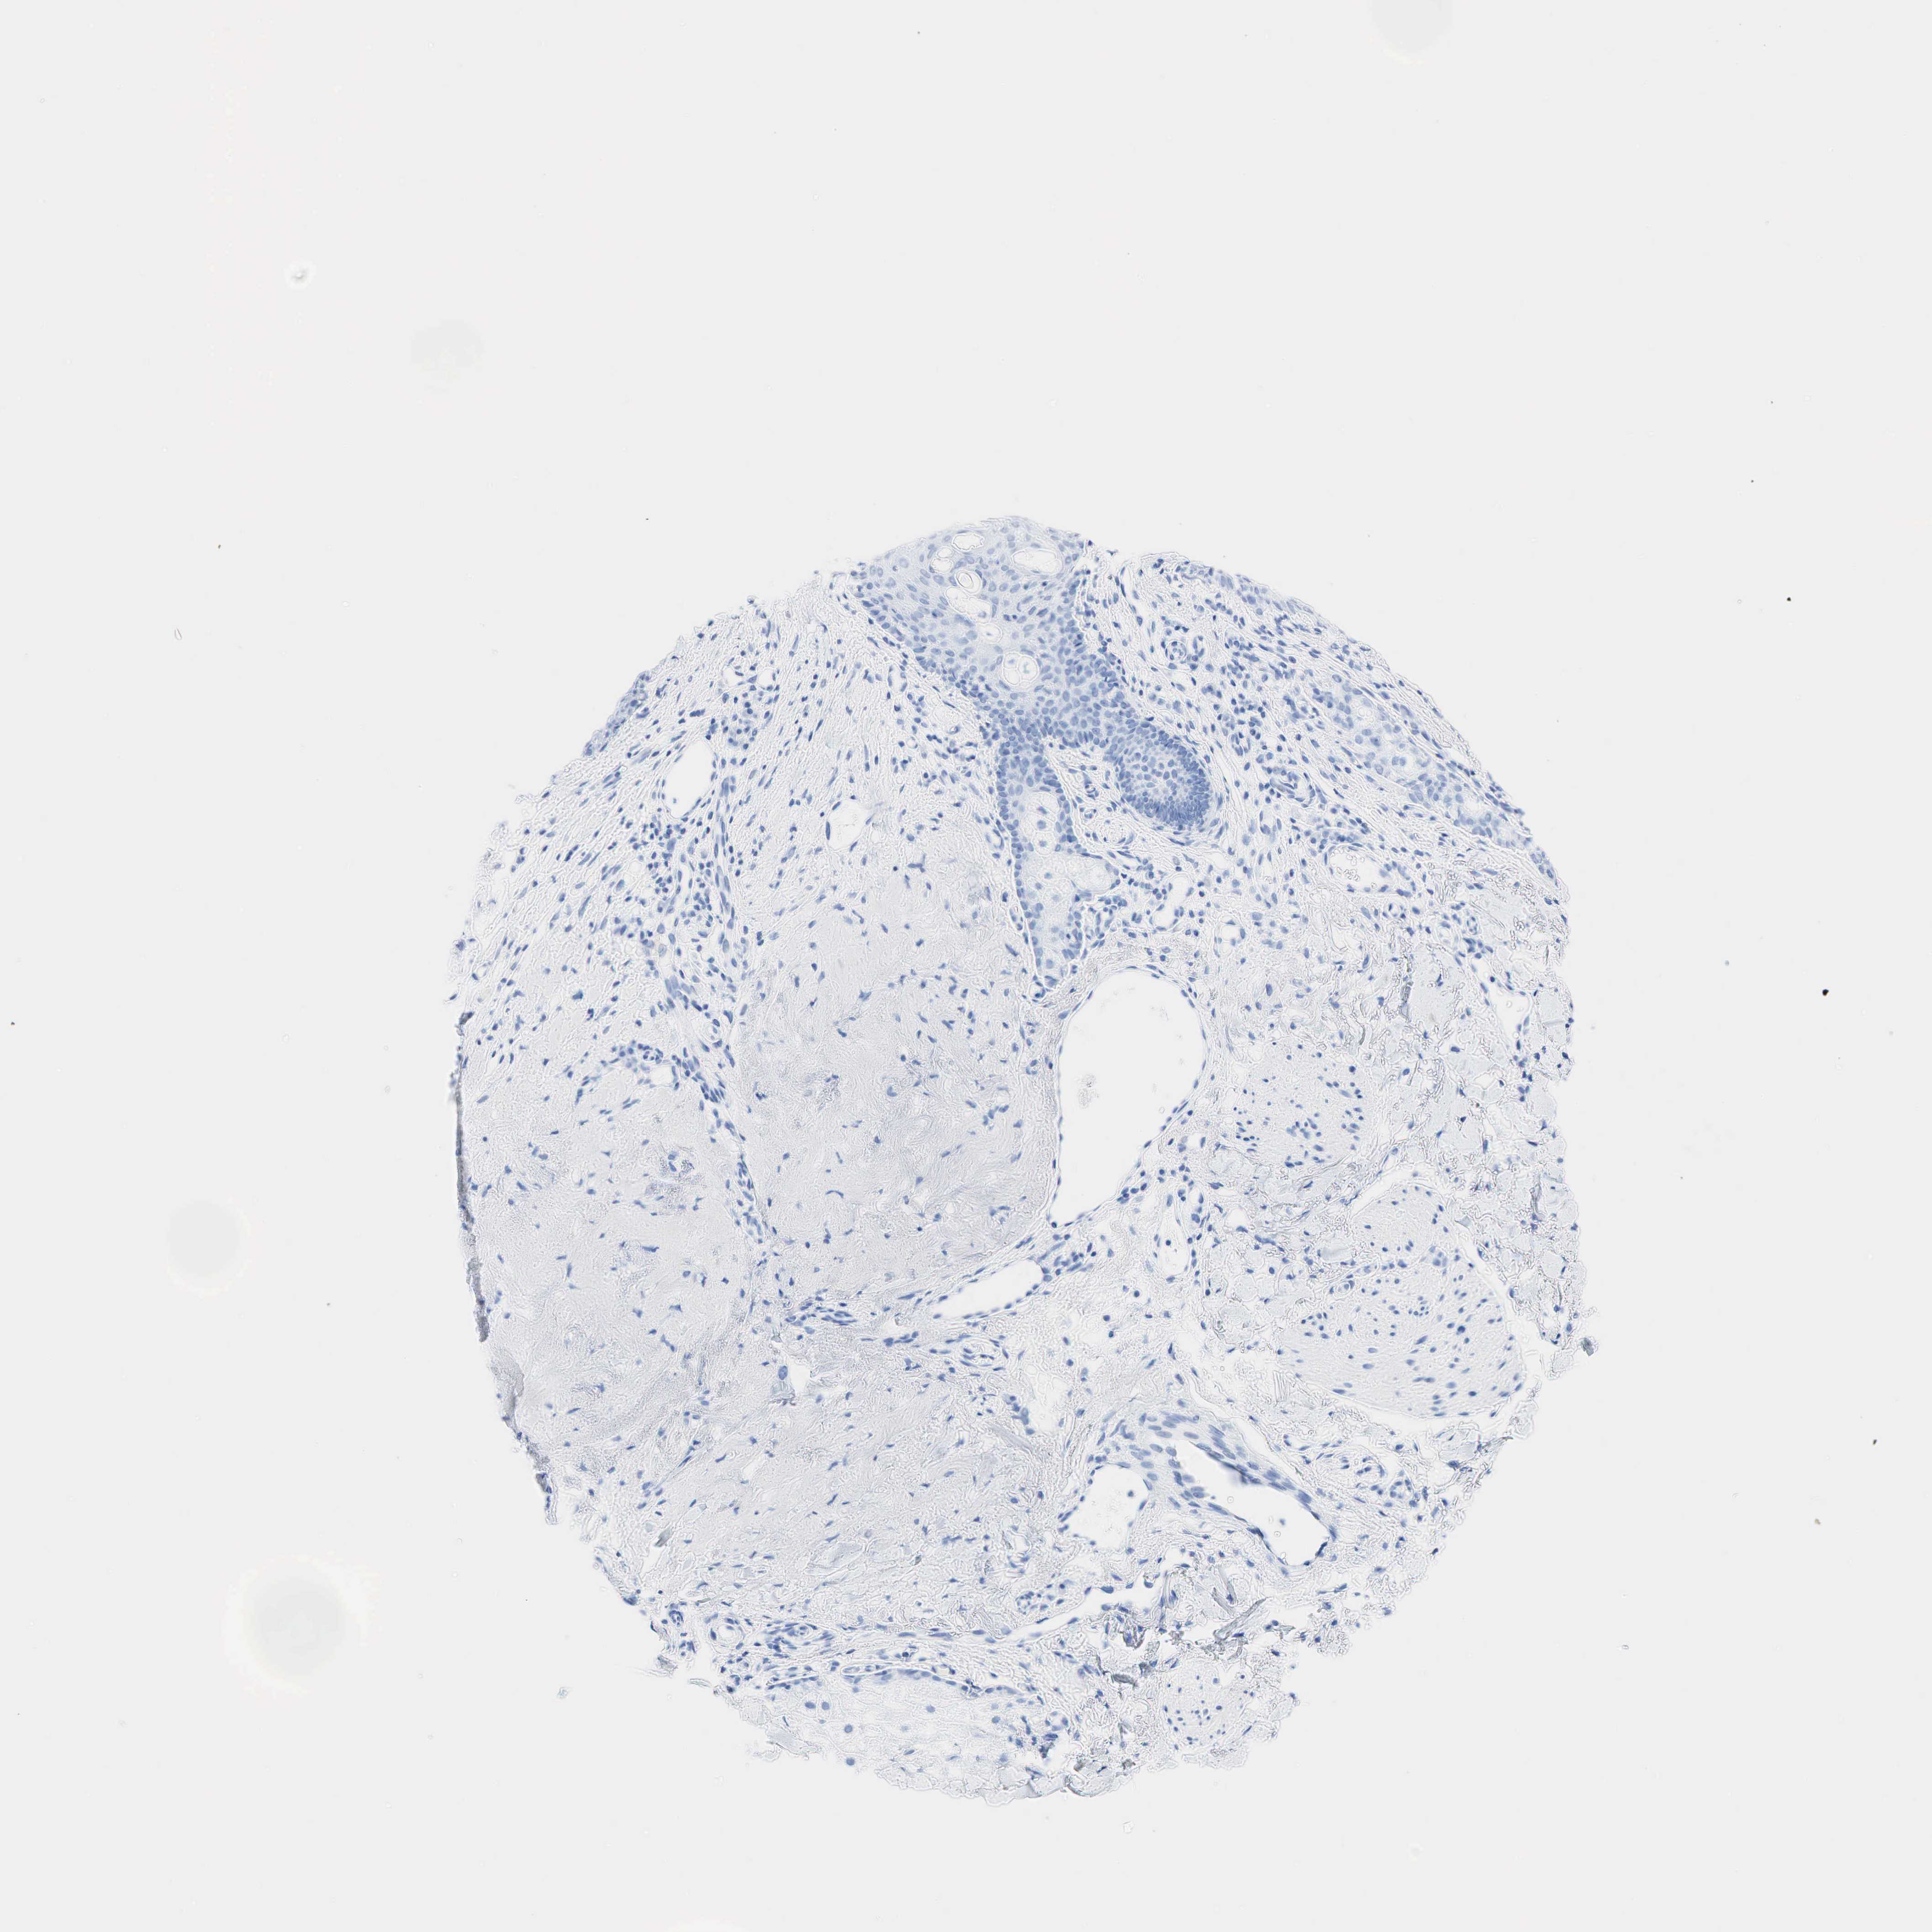

SKIN CANCER - Protein expressioni

A mouse-over function shows sample information and annotation data. Click on an image to view it in a full screen mode. Samples can be filtered based on level of antibody staining by selecting one or several of the following categories: high, medium, low and not detected. The assay and annotation is described here.

Antibody stainingi

Antibody staining in the annotated cell types in the current human tissue is reported as not detected, low, medium, or high, based on conventional immunohistochemistry profiling in selected tissues. This score is based on the combination of the staining intensity and fraction of stained cells.

Each image is clickable and will lead to virtual microscopy that enables deeper exploration of all samples and also displays staining intensity scores, fraction scores and subcellular localization as well as patient and tissue information for each sample.

Squamous cell carcinoma, NOS

Squamous cell carcinoma, metastatic, NOS

Basal cell carcinoma